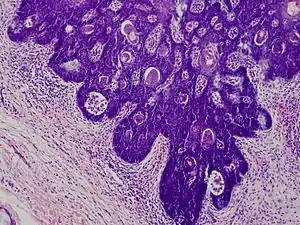

Folliculosebaceous cystic hamartoma

Folliculosebaceous cystic hamartoma abbreviated as (FSCH) is a rare cutaneous hamartoma consisting of dilated folliculosebaceous units invested in mesenchymal elements.[1]: 676 it typically affects adults, have a predilection for the central face or scalp, with less than 1.5 cm dimension.[2] Clinically, the lesions are asymptomatic, rubbery to firm in consistency, and usually occur on or above the neck in (> 90%) of cases, Histopathologically, FSCH shares several similar features to sebaceous trichofolliculoma, but it is usually possible to differentiate these two tumors.[3]